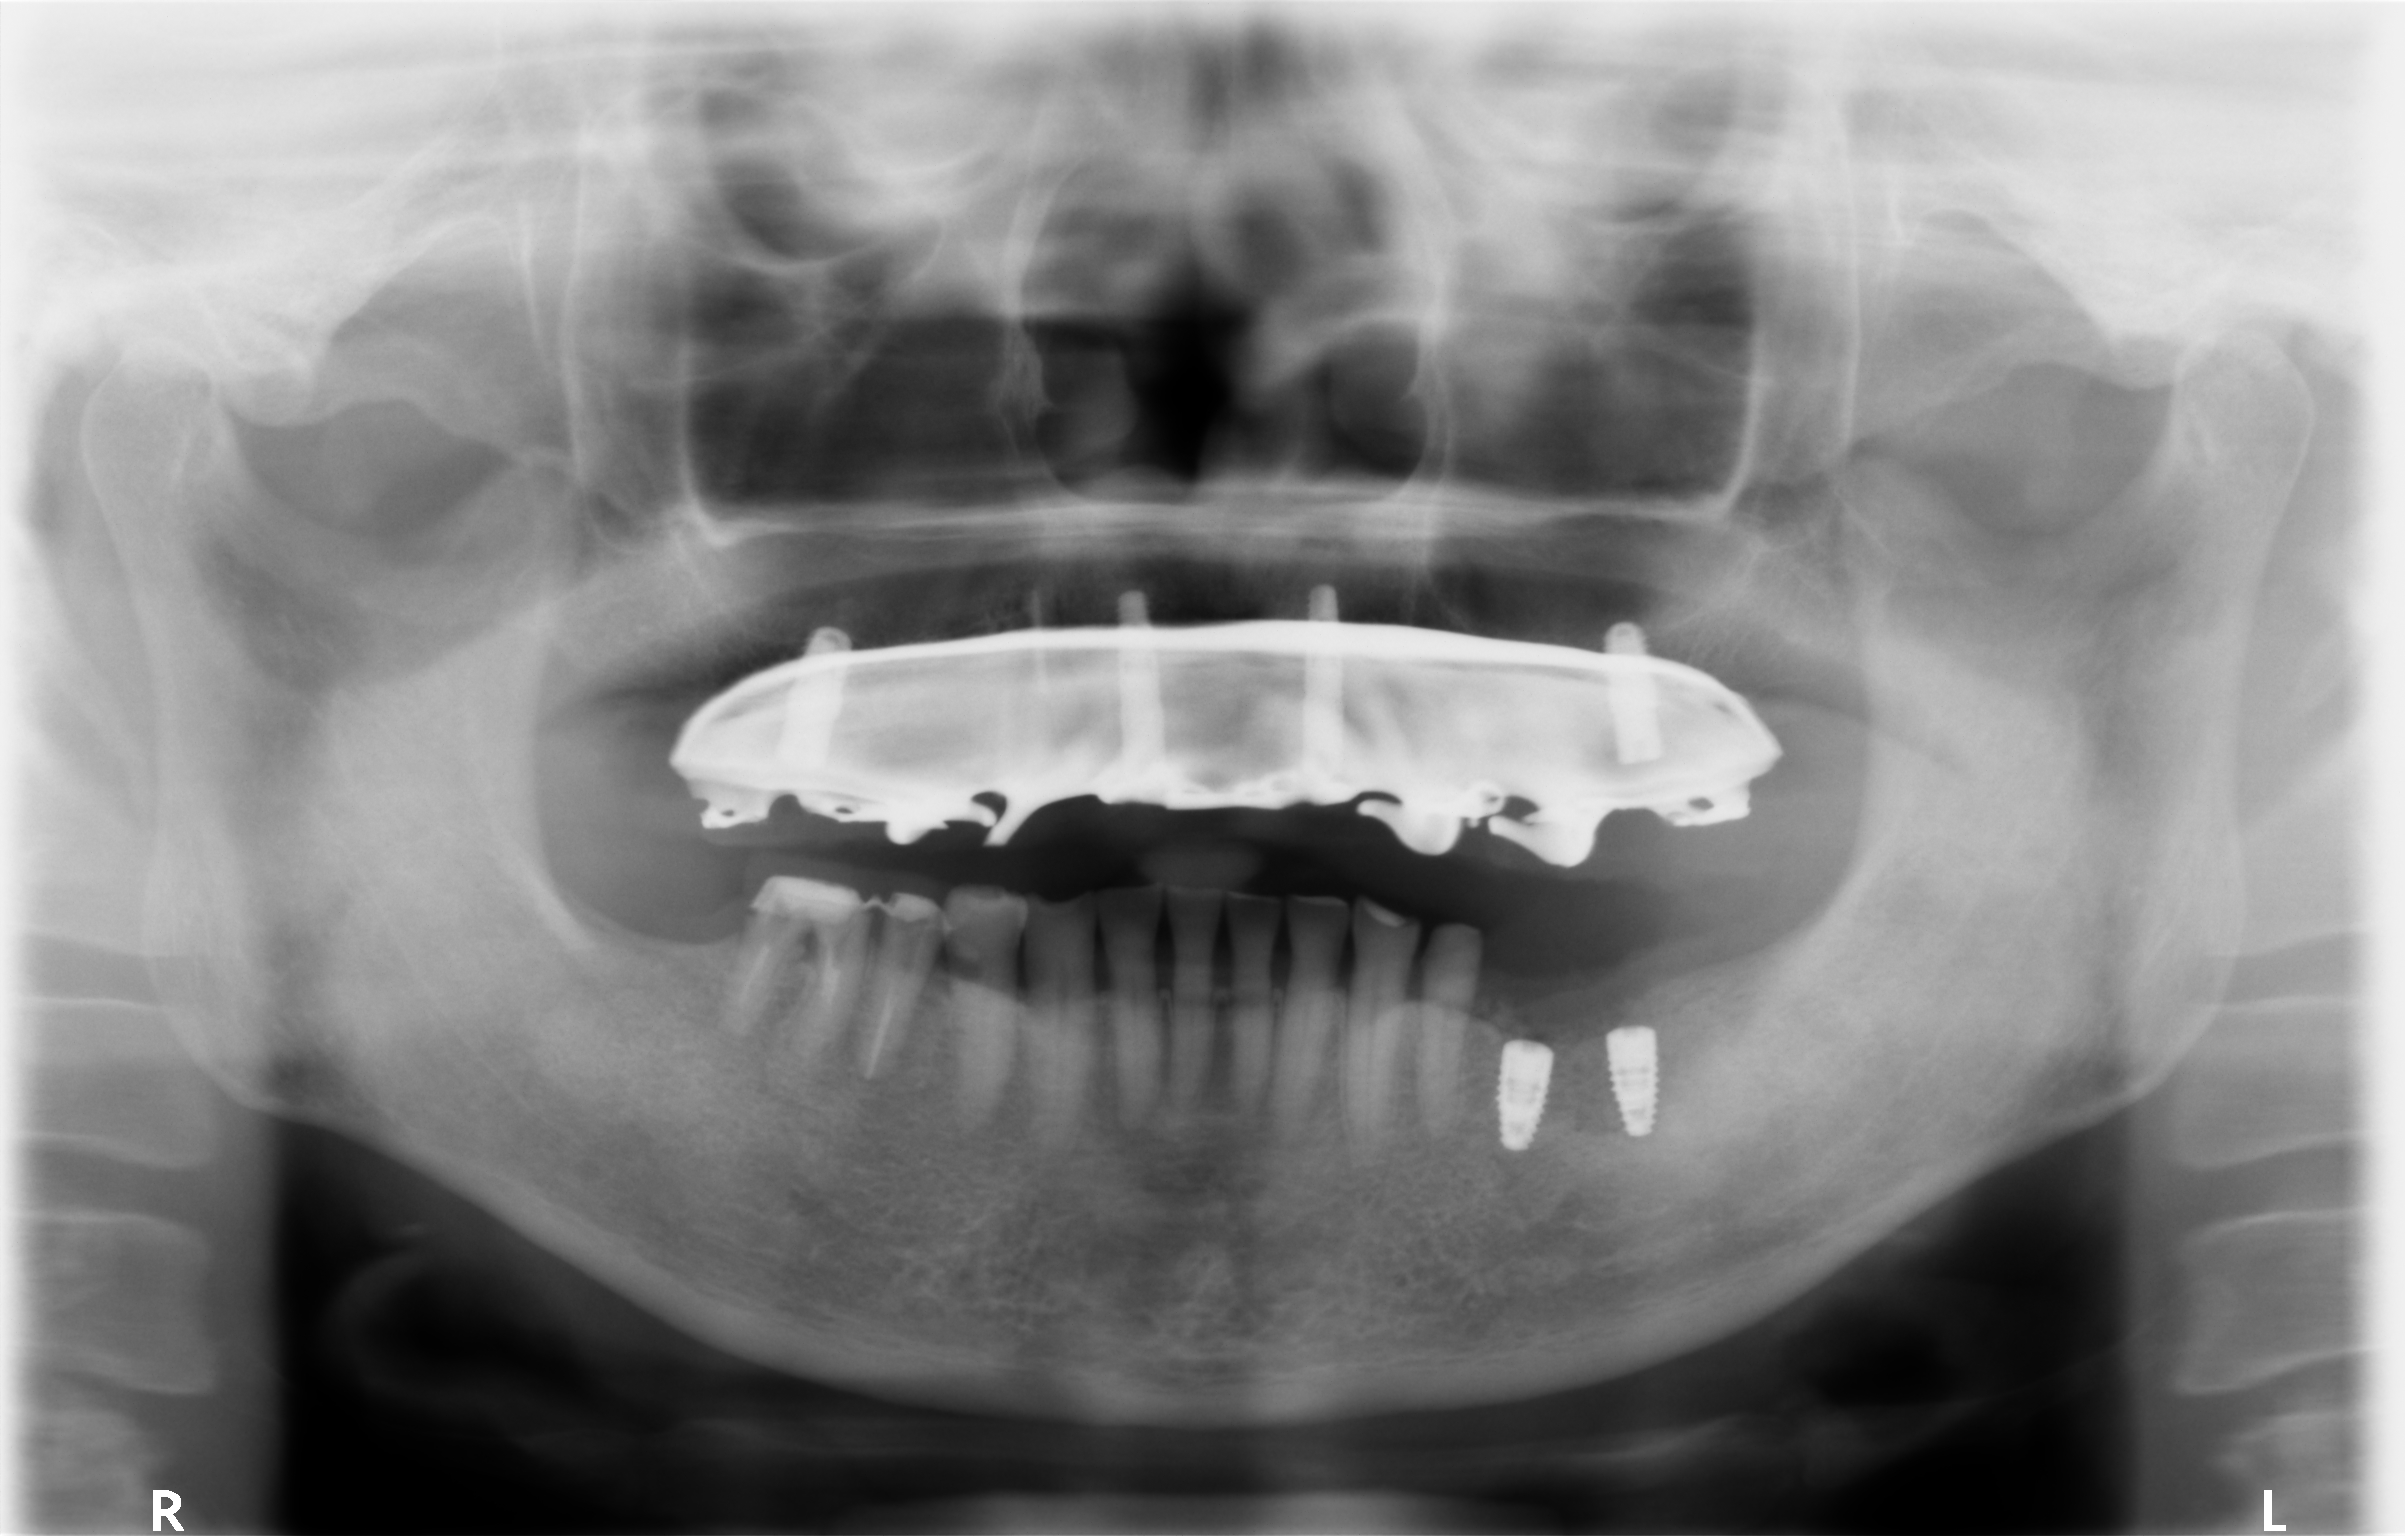

2.上顎をインプラントオーバーデンチャーへ変更

上顎はもともと部分入れ歯を使用されていたため、インプラントを用いたオーバーデンチャーへ移行することで、

安定性・噛み心地を大幅に改善できると判断しました。

今回使用したのは、精密性が高いコーヌステンチャー(ロケーター義歯よりも精密)。

■術後の状態

治療後の写真を見ると、上下ともに大きく審美性が改善し、笑顔の印象も自然になりました。

また、噛み合わせも安定し、患者さまからは「噛めるようになって本当に嬉しい」とのお声をいただきました。

今回採用したスクリューリテインは、セメント固定と比べて予後管理がしやすいのが大きな特徴です。

・もしインプラントを外す必要が生じた際でも、迅速に対応可能

・清掃性が高く、毎日のケアがしやすい

自然な噛み心地で噛めるため、入れ歯自体が消耗することはありますが、必要に応じて修理・新調が可能です。

インプラントも定期的なメインテナンスを継続できれば、一生使うことも可能です。

【5~6年後の実際の状態】

インプラントオーバーデンチャーは、一般的な入れ歯と比べて 噛む力が強く、安定性が高い のが大きな特徴です。

しっかり噛めることで、日常の食事の満足度が上がります。

また、使用していく中で必要があれば、人工歯の修理や新調が可能 です。

定期的に状態をチェックしながら、より良い状態を長く保つことができます。